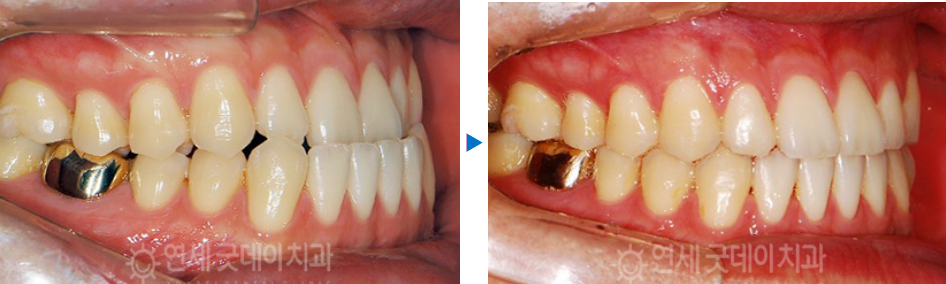

치료 전 - 치료 후

치료 전과 후를 한번에 살펴보게 되면

주걱턱 성향의 전형적인 옆모습이 개선되고,

물리지 않던 송곳니가 잘 물리고 있는

모습을 볼 수 있는데요.

결국엔 모든 치아가 뒤로 감으로써 윗니가

아랫니를 살짝 덮는 정상교합이 완성되었습니다.

치료기간은 대략적으로 1년 반정도 소요됐으며

사랑니발치 공간을 활용하여 정상교합으로

무사히 개선시켜드렸습니다.